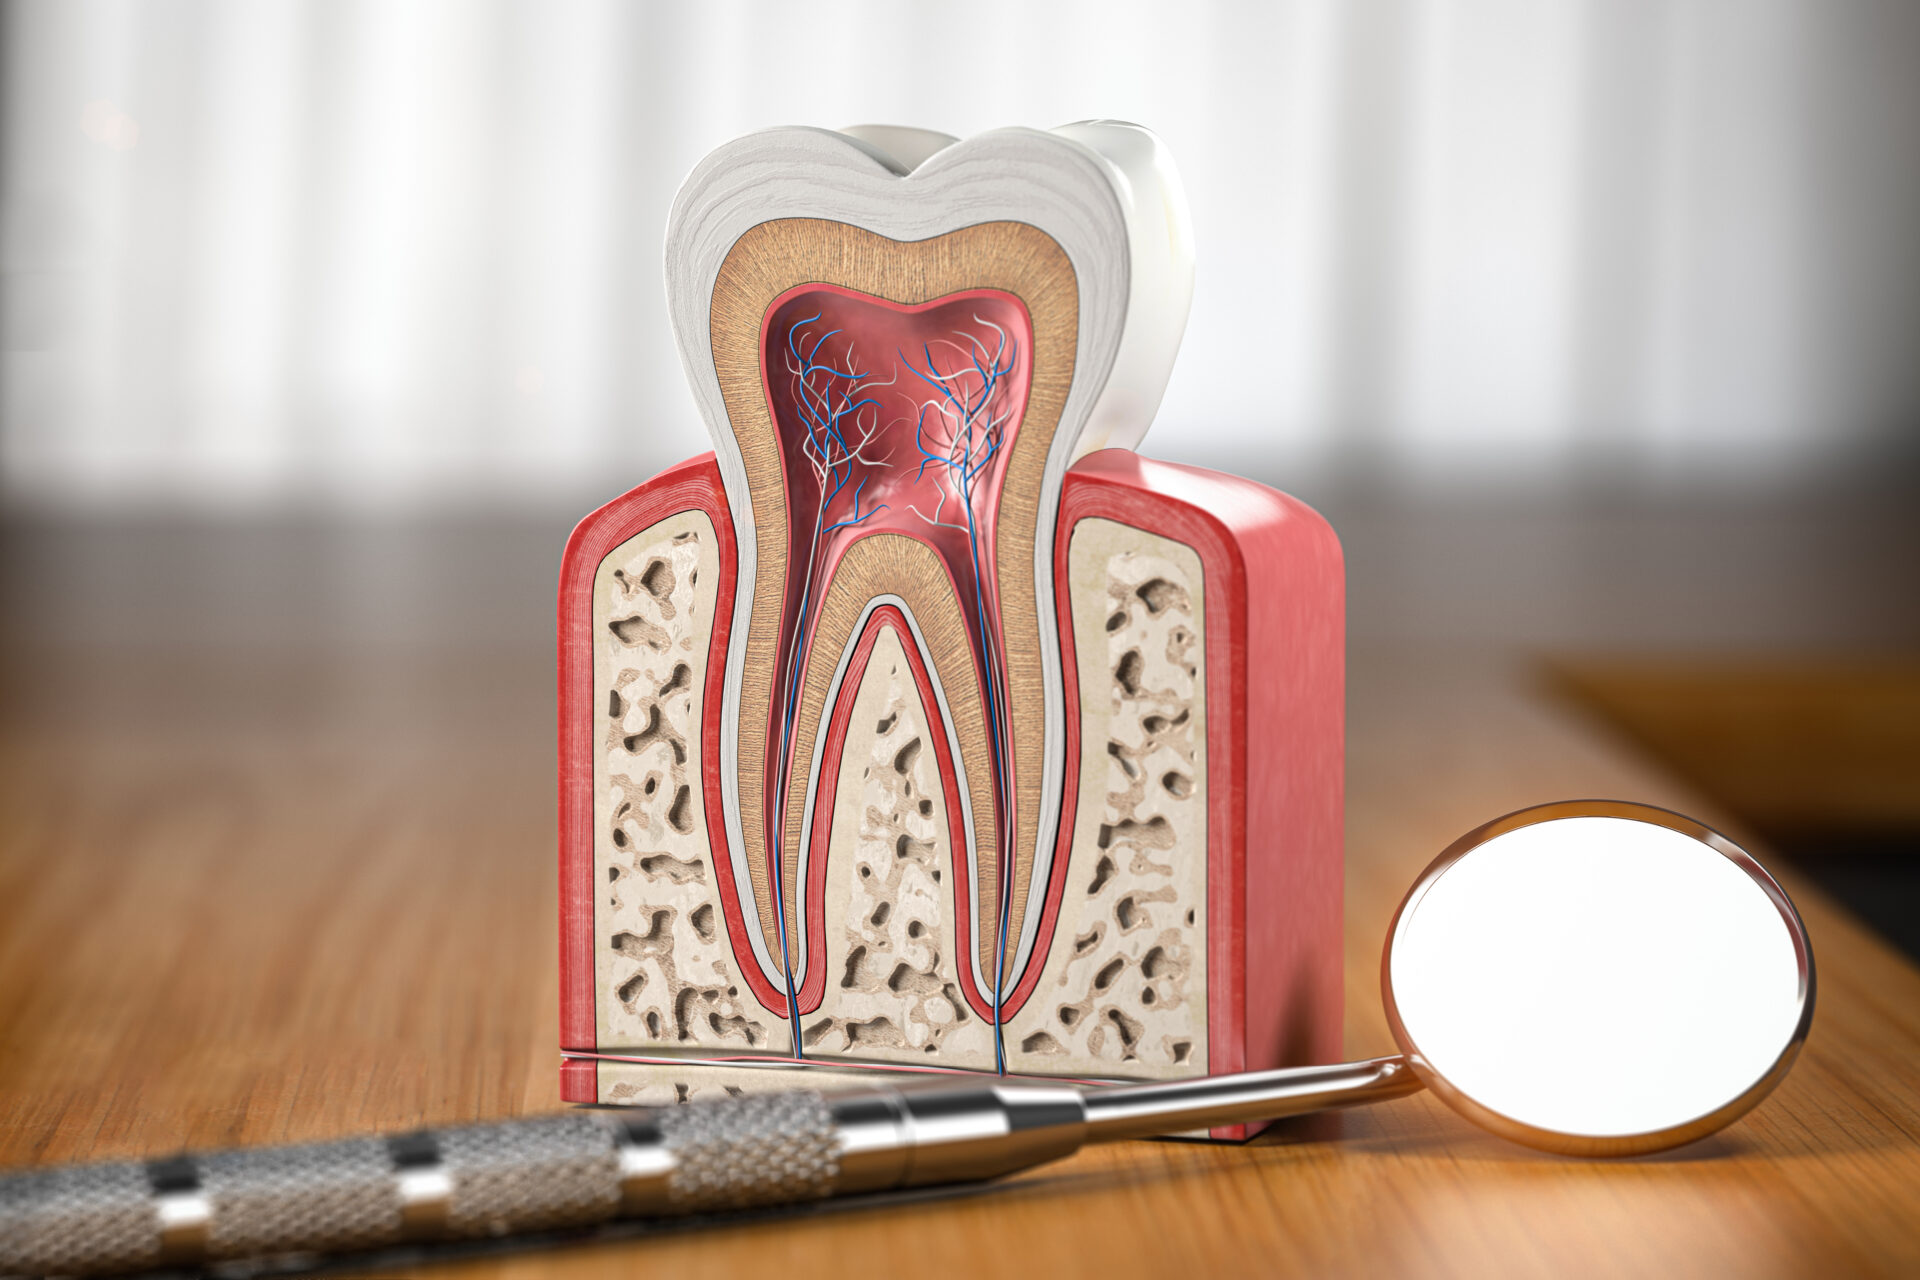

虫歯の進行状況は、大きく分けて四段階あります。まずは下記をご覧ください。

虫歯の進行状況によって治療内容は変わってきます。

皆様が虫歯治療でイメージされるのは、歯を削ってプラスチックの詰め物をする治療ではないでしょうか。これは上記C1~C2までの虫歯における話です。

しかしながら、C3~C4まで進行した虫歯は歯の神経まで達しており、「根管治療」という治療を行う必要が生じてきます。

根管治療とは、専用器具で虫歯に侵されてしまった歯や神経を除去し、歯の根の病気を治療する治療法のことです。この根管治療は、歯科医療のなかでも特に難しいジャンルであり、歯科医院によって治療の成功率が異なります。